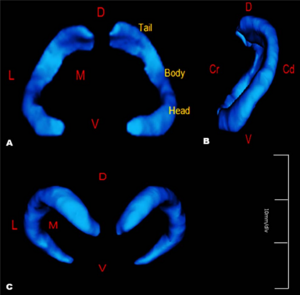

Potential of Diffusion Tensor Imaging and Relaxometry for the Detection of Specific Pathological Alterations in Parkinson's Disease (PD)

Publication: PLoS One. 2015 Dec 29;10(12):e0145493. PMID: 26713760 | PDF Authors: Esterhammer R, Seppi K, Reiter E, Pinter B, Mueller C, Kremser C, Zitzelsberger T, Nocker M, Scherfler C, Poewe W, Schocke M. Institution: Department of Radiology, University Hospital, Innsbruck Medical University, Innsbruck, Austria. Background/Purpose: The purpose of the present study was to evaluate the potential of multimodal MR imaging including mean diffusivity (MD), fractional anisotropy (FA), relaxation rates R2 and R2* to detect disease specific alterations in Parkinson's Disease (PD). We enrolled 82 PD patients (PD-all) with varying disease durations (≤5 years: PD≤5, n = 43; >5 years: PD>5, n = 39) and 38 matched healthy controls (HC), receiving diffusion tensor imaging as well as R2 and R2* relaxometry calculated from multi-echo T2*-weighted and dual-echo TSE imaging, respectively. ROIs were drawn to delineate caudate nucleus (CN), putamen (PU), globus pallidus (GP) and substantia nigra (SN) on the co-registered maps. The SN was divided in 3 descending levels (SL 1-3). The most significant parameters were used for a flexible discrimination analysis (FDA) in a training collective consisting of 25 randomized subjects from each group in order to predict the classification of remaining subjects. PD-all showed significant increases in MD, R2 and R2* within SN and its subregions as well as in MD and R2* within different basal ganglia regions. Compared to the HC group, the PD≤5 and the PD>5 group showed significant MD increases within the SN and its lower two subregions, while the PD≤5 group exhibited significant increases in R2 and R2* within SN and its subregions, and tended to elevation within the basal ganglia. The PD>5 group had significantly increased MD in PU and GP, whereas the PD≤5 group presented normal MD within the basal ganglia. FDA achieved right classification in 84% of study participants. Micro-structural damage affects primarily the SN of PD patients and in later disease stages the basal ganglia. Iron contents of PU, GP and SN are increased at early disease stages of PD. Funding:

The regions-of-interest (ROIs) were manually drawn by an experienced radiologist by using the b 1000 images, averaged for all measured directions, the FA maps and the proton-density weighted images. For that purpose, the maps of ADC, FA, R2 and R2* as well as the proton-density weighted images were first co-registered. The ROIs were segmented by syncing the b 1000 images, averaged for all measured directions, the FA maps and the proton-density weighted images in ImageJ. The ROIs were stored in the ROI manager and transferred to the co-registered maps. The segmented brain regions were highlighted in different colors: CN—black; PU—red; GP—green; TH—white; SN—blue; CC—cyan. The diffusion-weighted images, the R2 and R2*-weighted maps were transferred to the 3D Slicer software in order to co-register the R2 and the R2* maps as well as the MD and the FA maps |